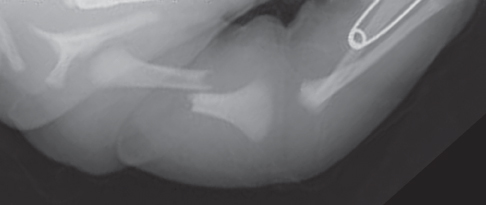

<p>A 5-year-old white boy had fever (temperature, up to 40.5ºC [105ºF]), progressive weakness of the lower extremities, and weight loss of about 3 kg over the past 3 weeks. During this time, he also...